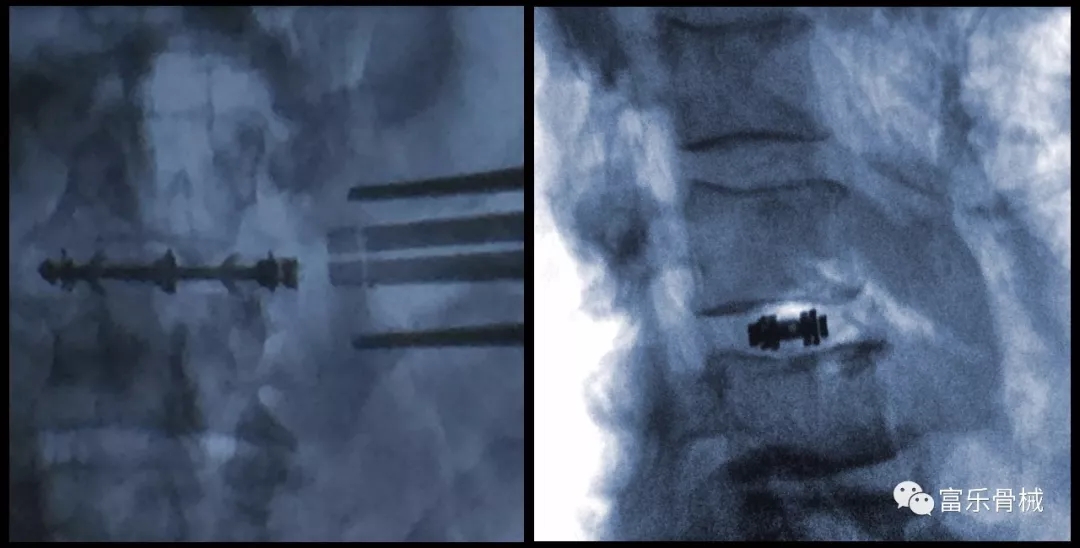

在随后的实操直播课程中,美国外科脊柱专家Patrick C. Hsieh直播演示了Uplifter膨胀式融合器的使用,并穿插讲解了该产品材料的优势与产品设计特点,成功通过DLIF术式完成了L3-L4阶段的椎体融合术。